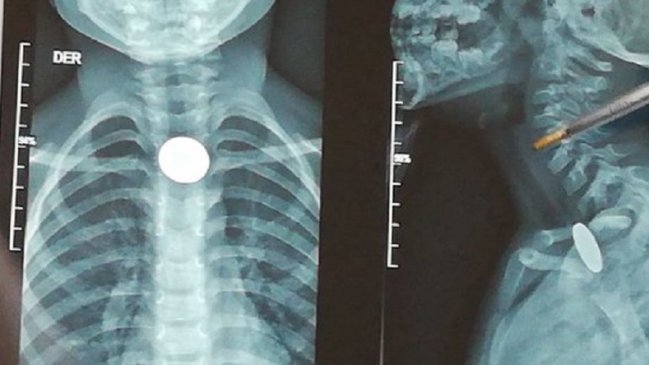

Niño se tragó una moneda y lleva una semana sin que se la puedan sacar

Un niño de cinco años se tragó una moneda en Santander, Colombia y lleva una semana sin que se la puedan extraer.

La situación le ha generado problemas respiratorios y de alimentación al menor, pues la moneda está estancada en el mismo lugar hace siete días.